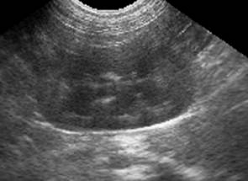

Рис.1. Ехотомограма нормальних нирок

у собаки (а - правої, б - лівої)

Як правило, легше виявити ліву

нирку, тому що вона розміщена більш каудально, і через це часто в якості

акустичного вікна можна використати селезінку.

Права нирка може бути ускладнена для

виявлення внаслідок її краніального положення і через те, що вона часто

затемнена газовмістними петлями кишечника. Ехогенність кори змінюється в

залежності від частоти датчика, від виду тварини та її розмірів.

У собак: ліва нирка є дещо

гіпоехогенною в порівнянні з селезінкою. Права нирка є ізо - або дещо

гіпоехогенною в порівнянні з паренхимою печінки при використанні датчика 5 МГц,

але може бути ізо - або гіпоехогенною при використанні датчика частотою 7,5

МГц.